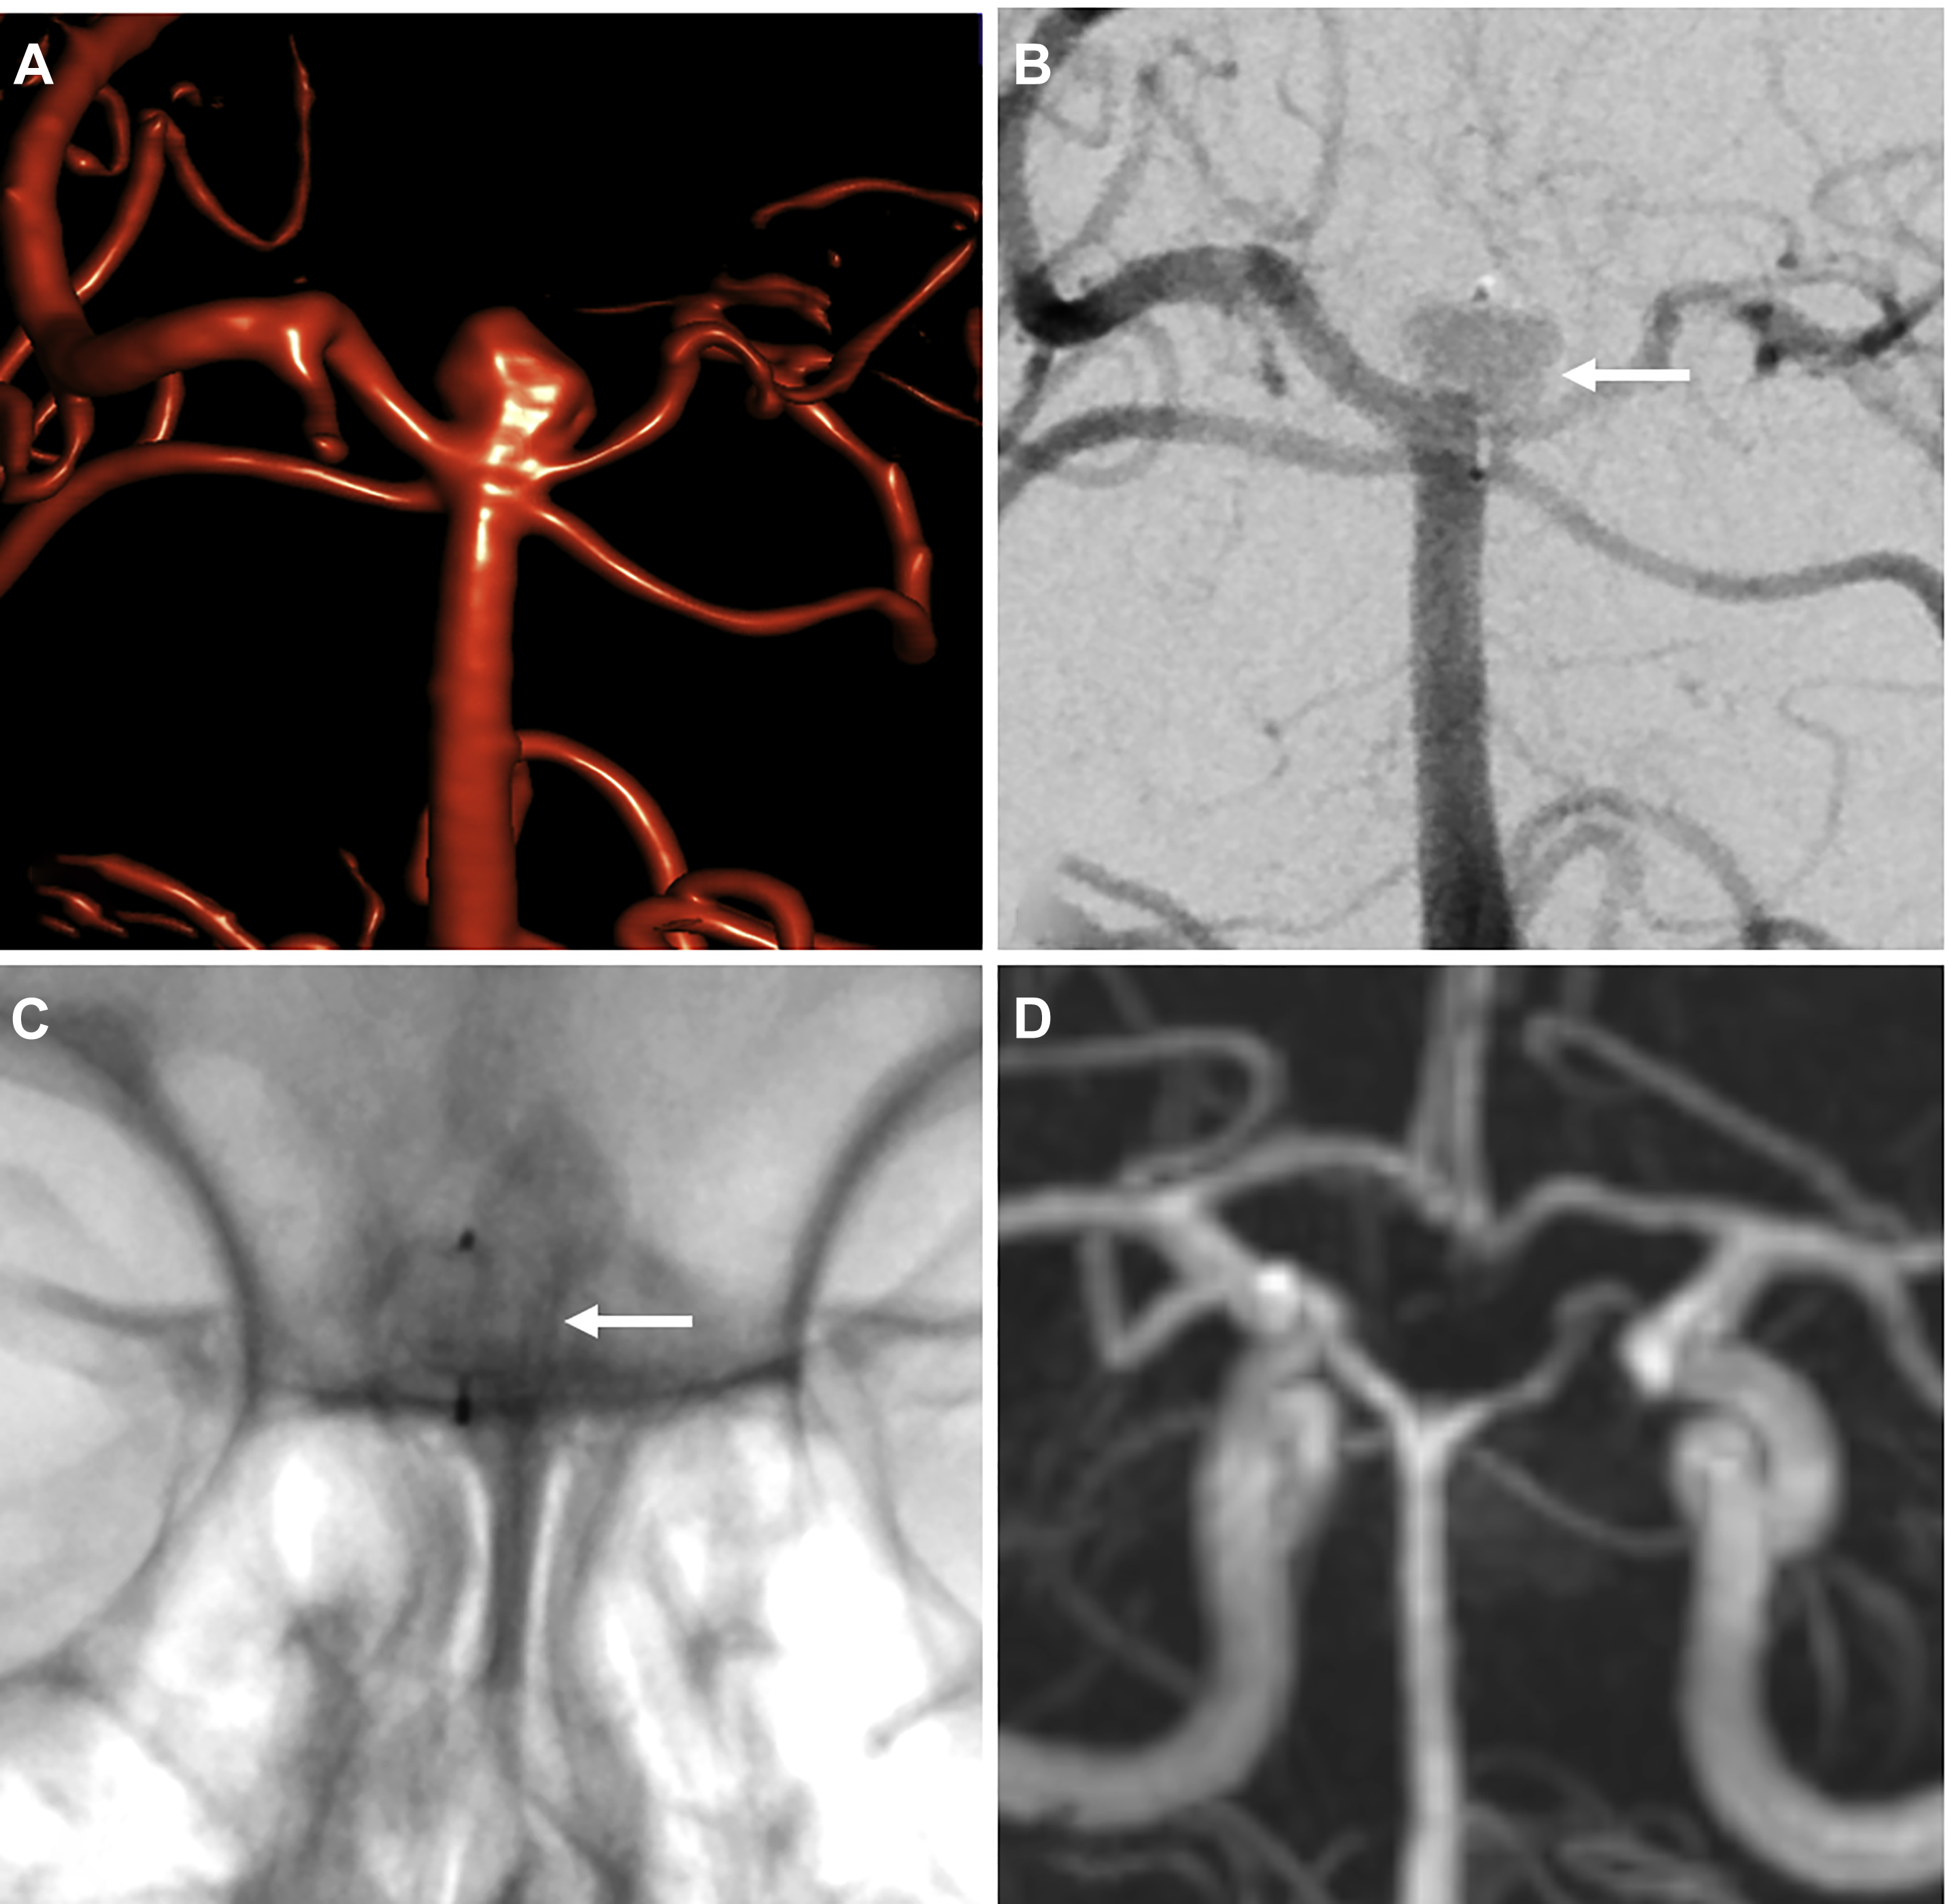

From www.frontiersin.org

Frontiers Surgical Clipping of Previously Coiled Recurrent Coiling Brain Aneurysm Surgery This procedure is also called endovascular embolization. Upmc is a world leader in. Endovascular coiling is a way to treat aneurysms without opening the skull or performing brain surgery. A brain aneurysm coil fills the aneurysm with platinum coils to help form a blood clot, sealing. Healthcare providers use endovascular coiling to block blood flow into an aneurysm. Brain aneurysms. Coiling Brain Aneurysm Surgery.

From www.researchgate.net

Surgical and endovascular treatments for cerebral aneurysm Coiling Brain Aneurysm Surgery Upmc is a world leader in. Endovascular coiling is a way to treat aneurysms without opening the skull or performing brain surgery. This minimally invasive procedure is the most common treatment option. The coil refers to a thin wire which is. A brain aneurysm coil fills the aneurysm with platinum coils to help form a blood clot, sealing. “clipping” is. Coiling Brain Aneurysm Surgery.